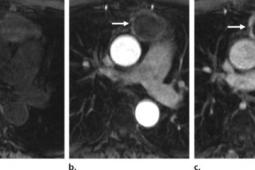

在医疗健康领域,胸部肿瘤的防治一直是备受关注的重要议题。近期,有一则令人醒的案例,一位患者体内被发现胸部存在厘米级别的肿瘤。这一...

东北首例心脏及肝脏联合移植手术在沈阳成功完成,这一重大医学突破不仅为东北地区的患者带来了生的希望,也标志着沈阳在器官移植领域取得...